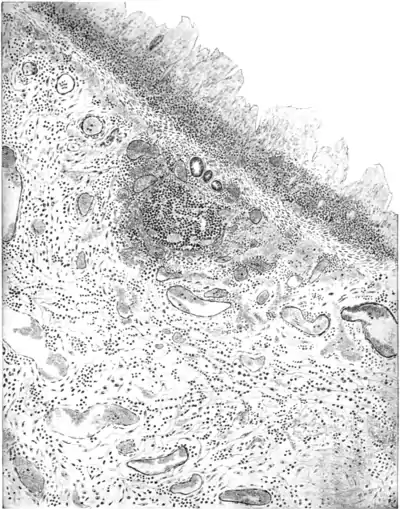

The microscopic pathology varies with the severity of the lesions. In the gangrenous form the epithelial cells of the mucous layer can no longer be distinguished, the whole of the mucous membrane undergoing coagulation necrosis with destruction of the glandular elements. The muscularis mucosse may be intact, or in places destroyed. The outstanding feature is the infiltration of the submucosa (Plate VIII.) and destruction of the nutrient blood-vessels. (These appearances are very similar to those produced in the large intestine of rabbits by intravenous injection of dysenteric toxins.) In subacute cases portions of the crypts can still be distinguished, but the cells stain badly and are vacuolated, and the submucosa is invaded by large wandering plasma cells, liable in sections to be mistaken for amœbæ. Dysentery and other bacilli can be seen crowding the mucous layer and in the lymphoid follicles, but bacilli are not found in the subinucous layer save where there is a break in continuity of the muscularis mucosæ. The muscular coat is normal.

Microscopical section of the large intestine in bacillary dysentery, showing necrosis of the mucosa, cellular infiltration and hæmorrhages into the submucosa. (After Bahr.)

Plate VIII.